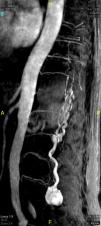

Contrast-enhanced magnetic resonance angiographic image. Sagittal plane with maximum intensity projection reconstruction. The image shows the mass, as well as the dilated vascular structures. Because of the static nature of the examination, the view does not show the origin of the blood supply.